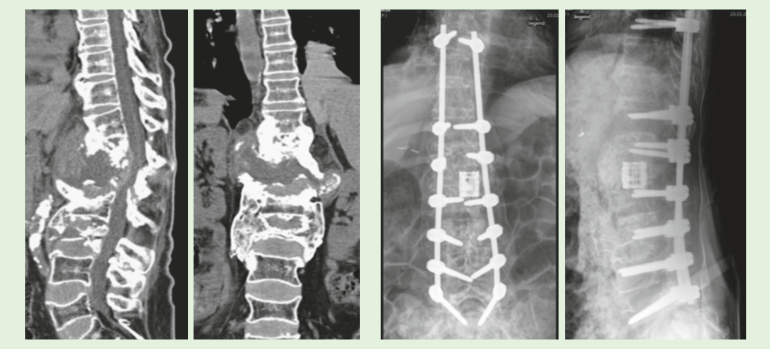

Neuroarthropathie: Unmerkliche Abnutzung von Wirbelsäule und Gelenken

Menschen mit Querschnittlähmung können im Laufe der Jahre eine Neuroarthropathie entwickeln. Eine heimtückische Erkrankung, die sich unmerklich in die Gelenke und die Wirbelsäule einschleicht und Deformationen und Instabilität zur Folge haben kann. Entstehungsursache sind eine gestörte Schmerzwahrnehmung und daraus resultierende mangelnde Haltungsregulierung.